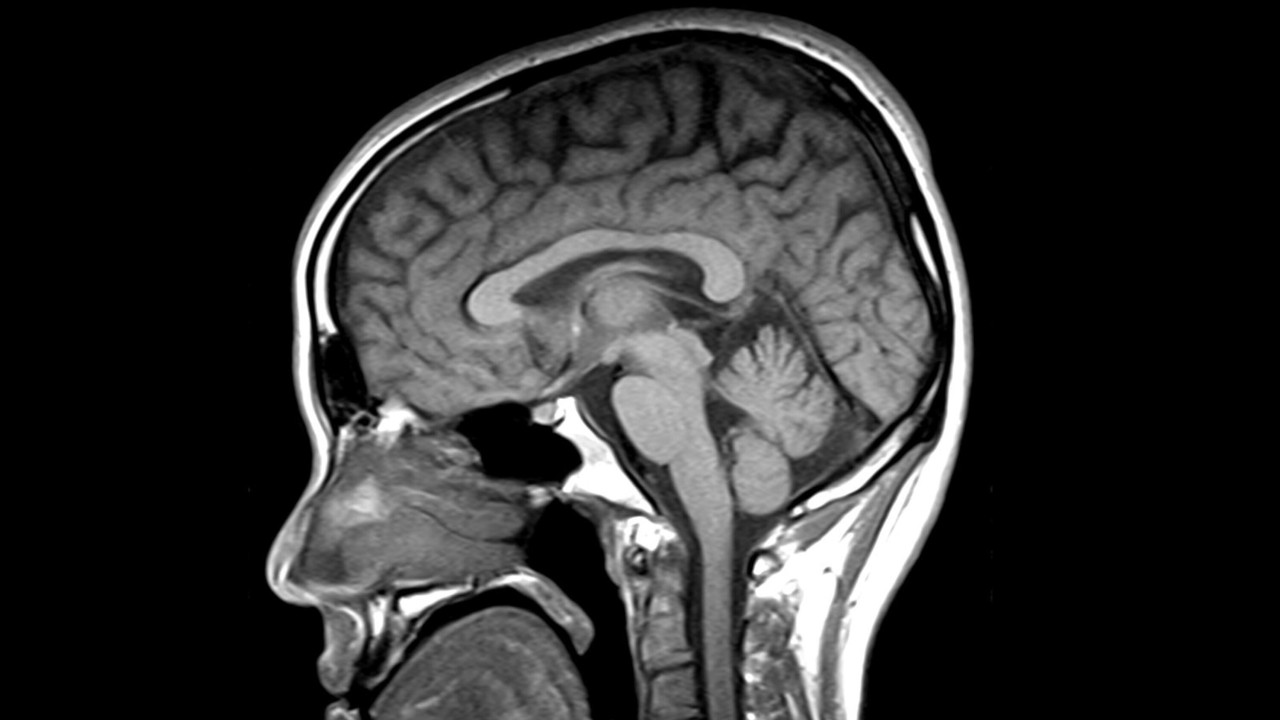

Un estudio liderado por el Instituto de Investigación Sant Pau (IR Sant Pau), en Barcelona, demuestra que la resonancia magnética puede identificar con mayor precisión la parálisis supranuclear progresiva (PSP) y la degeneración corticobasal (CBD), dos enfermedades infradiagnosticadas. Además, permite seguir su evolución de forma objetiva y mejorar el diseño de ensayos clínicos. El trabajo fue publicado en The Journal of Prevention of Alzheimer’s Disease.

La resonancia magnética resulta clave para entender enfermedades como la PSP y la CBD, que forman parte de las taupatías, un grupo de trastornos neurodegenerativos relacionados con la acumulación anómala de la proteína tau.

El estudio demuestra que la resonancia magnética parkinsonismos atípicos permite identificar “firmas cerebrales” específicas de cada enfermedad, incluso en etapas tempranas.

A través del análisis de la atrofia cerebral, los investigadores han logrado diferenciar entre PSP y CBD con alta precisión.

- En PSP: afectación del tronco encefálico y estructuras profundas

- En CBD: mayor daño en áreas corticales relacionadas con el movimiento

«Aunque clínicamente puedan parecer muy similares, a nivel cerebral la PSP y la CBD dañan el cerebro de forma diferente», señala el Dr. Ignacio Illán-Gala, investigador del grupo de Neurobiología de las Demencias del IR Sant Pau y neurólogo del Hospital Sant Pau, y autor sénior del estudio.